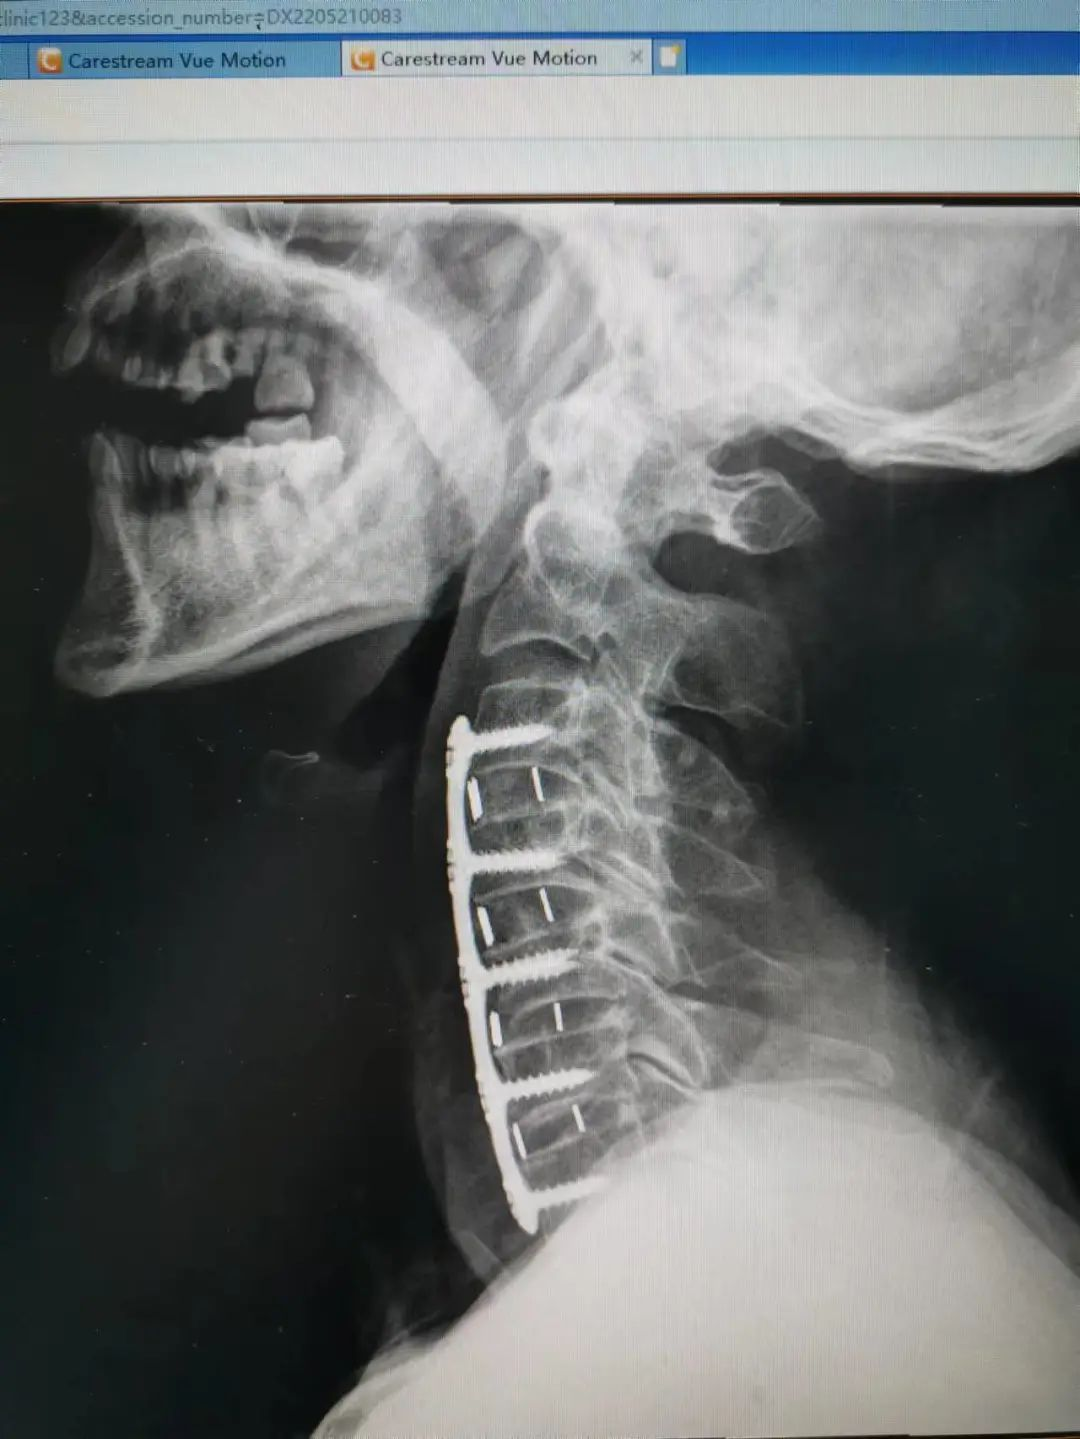

楊先生脊髓性頸椎病拍片

由于楊先生的病情嚴重,需住院治療。楊先生入院后,瀘州市中醫(yī)醫(yī)院骨傷二科科主任楊陳一制定了手術(shù)計劃,決定脊髓型頸椎病的手術(shù)從前路切開減壓,頸3/4 、頸4/5、 頸5/6、 頸6/7椎間盤切除,椎間融合,鋼板內(nèi)固定術(shù)手術(shù),而腰椎管狹窄癥經(jīng)后路切開減壓,腰3/4、腰4/5椎同盤動除,椎間融合、釘棒系統(tǒng)內(nèi)固定術(shù)。